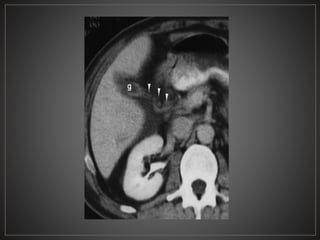

CPRE: Dilataciones saculares de CBIH. TC: Simple:Áreas redondas, hipointensas en topografía de CBIH. Contraste: Signo del punteado central. RM: T2: Espacios quísticos hiperdensos

• #47 Axial ventana tejidos blando fase portal, se observan multiples imágenes de morfología ovalada, de bordes definidos, hipodensa, correpondiente a quistes intrahepaticos y un quiste grande extrahepatico - tipo IVa

• #53 El CT axial con contraste muestra una dilatación masiva de los conductos biliares intrahepáticos. punto "central" o "excéntrico" en muchas de las estructuras quísticas, que representan las venas portas, un clásico hallazgo de imágenes en la enfermedad de Caroli.

• #54 CT contrastada fase portal, observan imágenes hipointensas con un centro hiperintenso en relación a dilatación sacular árbol biliar (central dot)